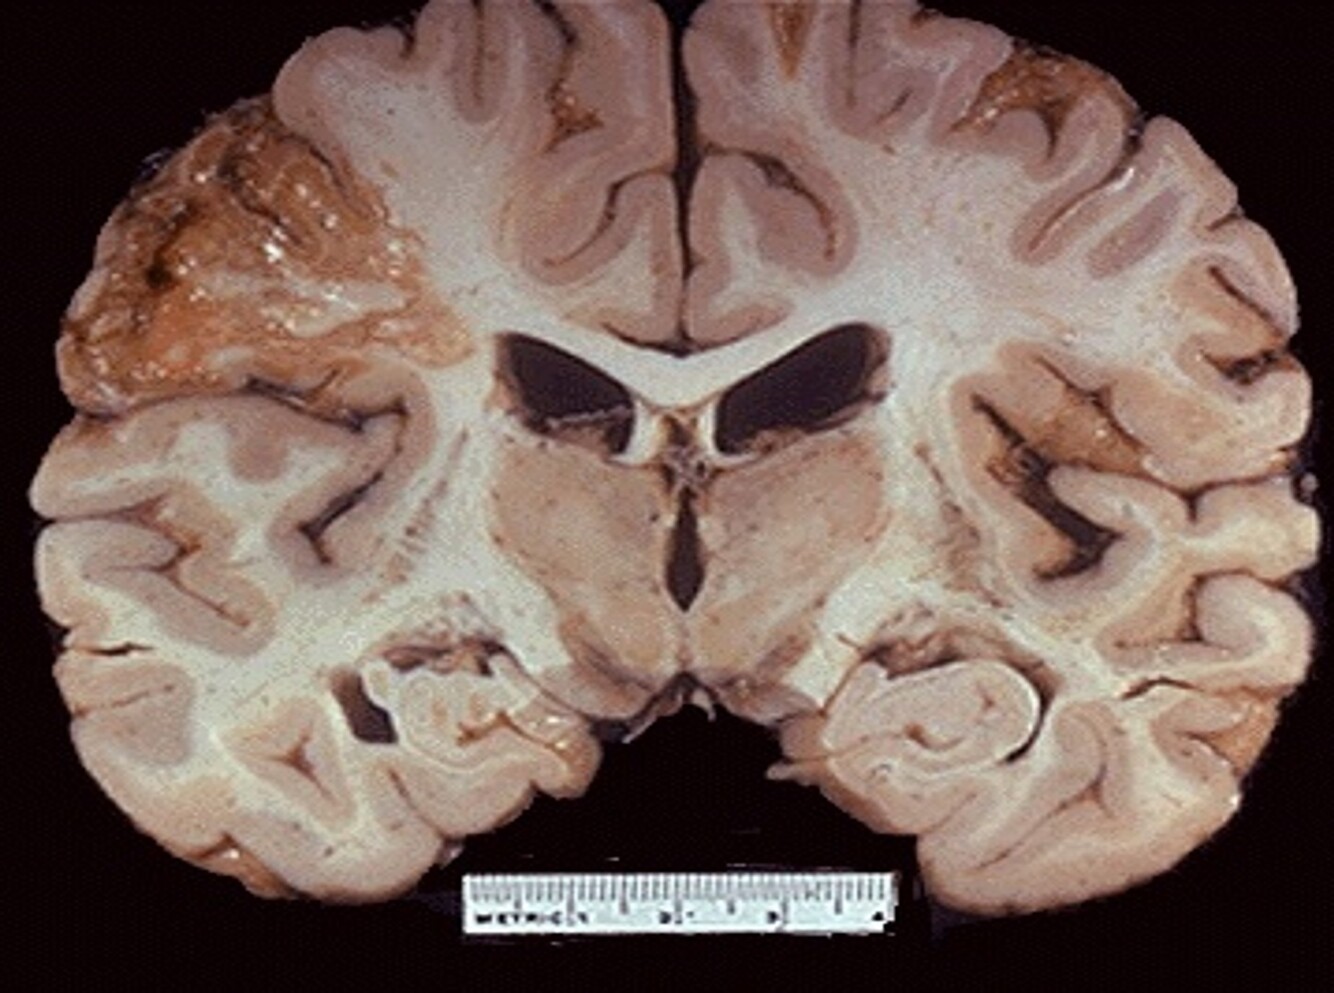

Liquefactive necrosis (brain)

Liquefactive necrosis; Stroke/Ischemic Stroke/Ischemic Infarction Cell Morphology: Pale areas showing pale infraction, otherwise would be red for haemorrhagic infarction. Loss of neurons and neuroglial cells, clear space seen.

Patient comes in with stroke like symptoms, contralateral lesion to where the injury is. CT scan will reveal that the patient had a stroke. Biopsy will be taken and shows the images above. Focal loss of blood supply to the portion of cerebrum.

Liquefactive necrosis